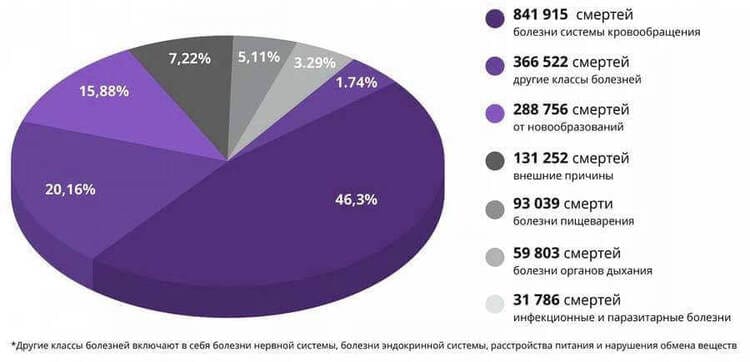

Сердечно-сосудистые заболевания — это №1, мировые лидеры среди болезней по количеству жизней, которые они забирают. 94% инфарктов и инсультов происходят из-за повышенного давления. В 89% случаев гипертония при инфаркте и инсульте заканчивается летальным исходом.

Если говорить о конкретных значениях, то гипертония является причиной приблизительно 77-78% смертельных «естественных» исходов. В абсолютных цифрах — это около 9 млн смертей в прошедшем, 2023 году, а вы забиваете головы и вводите невероятные меры из-за менее распространенных заболеваний!

Статистика шокирует! По прогнозу ВОЗ, в 2030 году от сердечно-сосудистых заболеваний умрет около 23,6 млн человек!